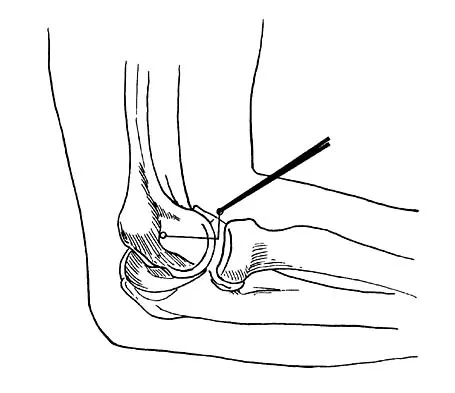

A 16-year-old boy with osteochondritis dissecans of the capitellum has intermittent symptoms of catching and locking. Examination is unremarkable. Radiographs reveal a loose body anteriorly with a diameter of 10 mm. To remove the loose body, elbow arthroscopy is being considered. Which of the following procedures would minimize the risk of neurovascular complication during the procedure?

Explanation